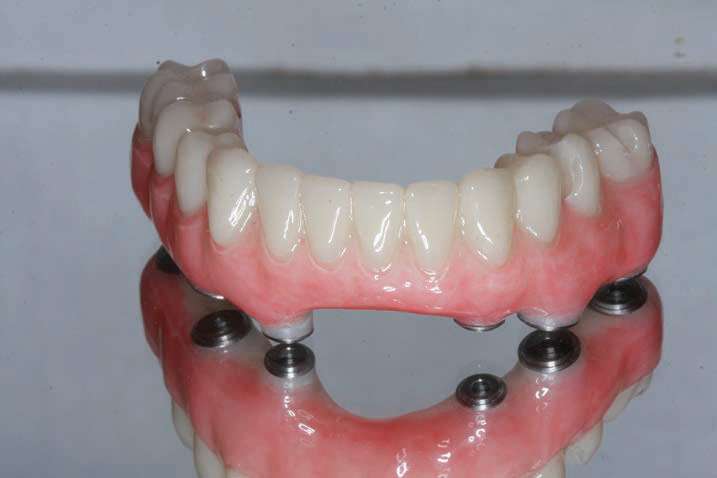

At this time, the patient suffered a stroke and lost some of the dexterity in his hands. It became evident when observing the patient’s difficulty in cleaning the PMMA provisional implant prosthesis, that he would require help from his wife. In addition, the gingival embrasures would need to be opened up more to allow for easier access with at-home cleaning aids (such as GUM Proxabrush Go-Betweens Cleaners [Sunstar Americas] and Waterpik). Instructions for these prosthetic design modifications were submitted to the dental lab, which sent updated CAD design images for clinician approval, prior to finalization of the prosthesis. After review, the digital design was modified until we had a cleansable gingival surface for the BruxZir Solid Zirconia Full-Arch Implant Prosthesis (Figures 18a to 18d). An additional PMMA provisional implant prosthesis was fabricated and delivered to confirm these final design changes; it had an almost Roman aqueduct appearance to the gingival surface of the prosthesis (Figure 19).

The final monolithic zirconia restoration was fabricated based on the same digital design as the approved PMMA provisional, allowing the patient and his wife easy access for all cleaning implements. The patient had little food impaction and was comfortable with his border movements and ability to really cut and chew his food.

The completed BruxZir Full-Arch Implant Prosthesis is the culmination of great communication with the dental lab team. The final prosthetic result ensured that the patient would not only enjoy his new bridge but would also be able to clean and maintain it with one hand (Figure 20). The relaxed smile view and postoperative Panorex (Figures 21 and 22) shows appropriate lip and tooth display and was a vast improvement over his removable lower denture. The full-face, postoperative photo (Figure 23) of the pleased patient demonstrates that the dictates of aesthetic rehabilitation were met.